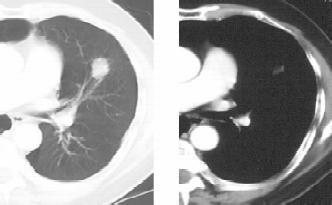

图1-1 男性,32岁,干咳发热1个月,急性血行播散型肺结核

(2)血行播散型肺结核:本型是各型肺结核中较严重者,是急性全身血行播散型结核病的一部分;多由原发型肺结核发展而来,但成年人大多由肺外结核病灶破溃至血管所引起。本病起病急,有全身毒血症状,常伴有结核性脑膜炎;X线显示双肺在浓密的网状阴影上满布境界清晰的粟粒状阴影,直径约2mm,大小及密度均大体相等(图1-1)。病初胸部X线表现可能无明显粟粒状影,或仅有弥漫性网状改变,易误诊为伤寒、败血症等其他发热性疾病。若人体抵抗力较强,少量结核菌分批经血液循环进入肺部,则血行播散灶常大小不均、新旧不等,在双肺上中部呈对称性分布,称为亚急性或慢性血行播散型肺结核。其病情发展缓慢,通常无显着中毒症状。患者可无自觉症状,偶于X线检查时才被发现。此时病灶多较稳定或已硬结愈合。